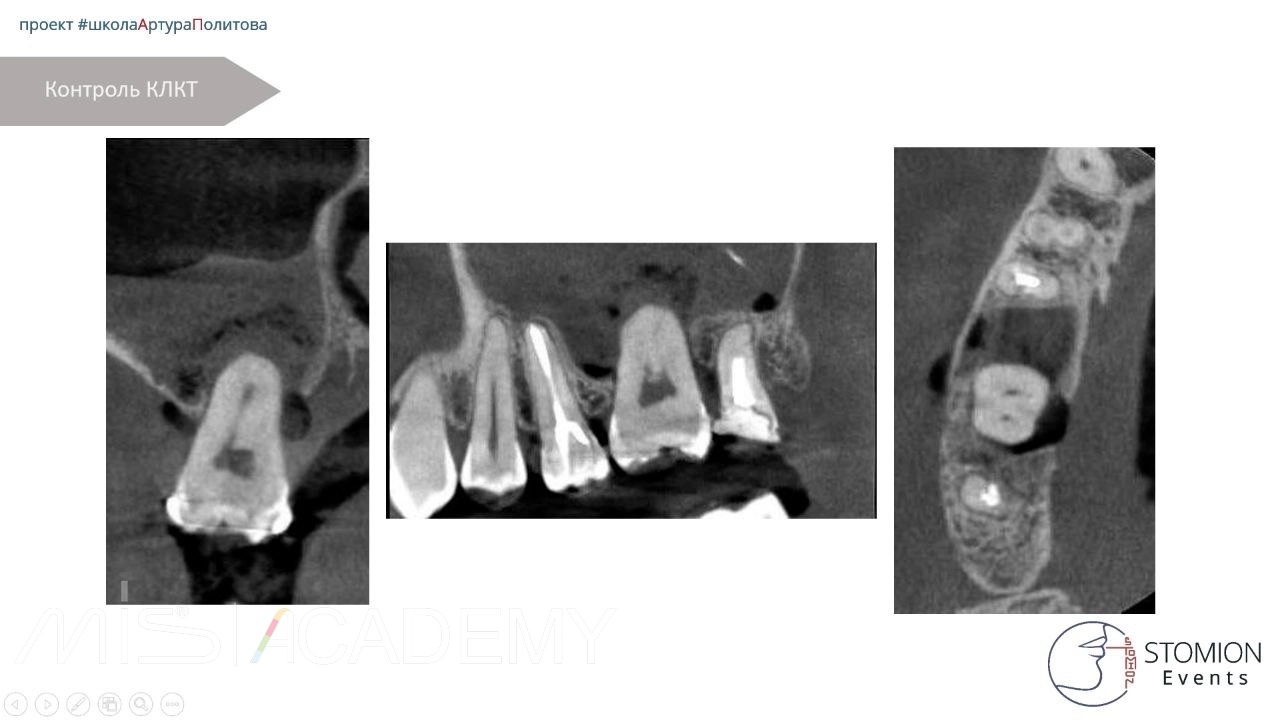

• Контрольное КЛКТ.

• Через 6 месяцев — контрольное КЛКТ и осмотр.

• Исход положительный, костная регенерация и интеграция трансплантата.